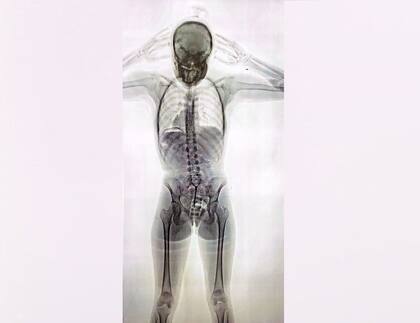

El 3 de agosto de 2023 se conoció la noticia de la detención de la “mula” narco cuando se hicieron públicas las imágenes captadas por un equipo de rayos X Body Scan que mostraban cómo se veían las 78 cápsulas con cocaína en el cuerpo de la joven pasajera.